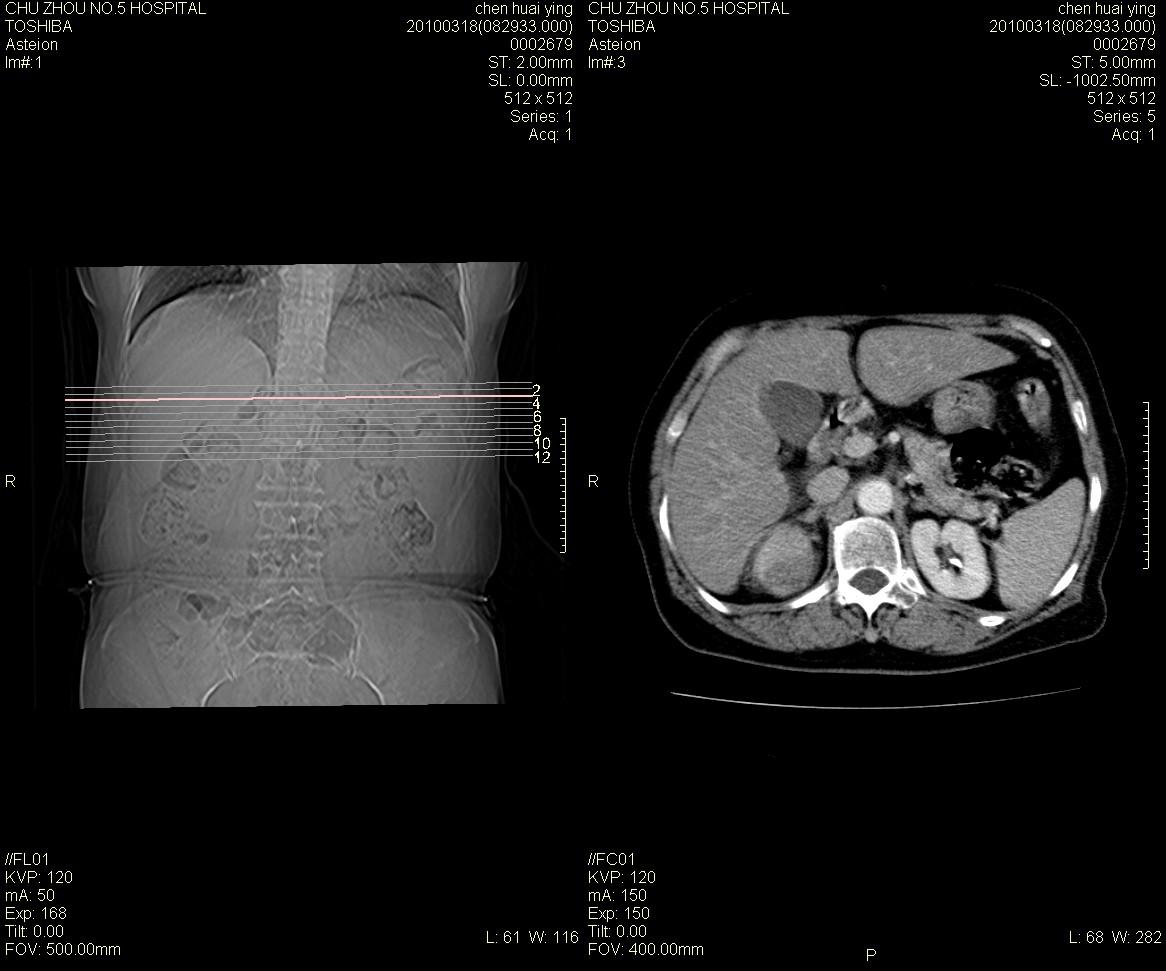

标题: CT25148 肾上腺增强

ct25148增强图片

动脉期太早了,扫的有点低。考虑良性占位右侧肾上腺嗜铬细胞瘤并坏死囊变可能性大,神经鞘瘤不排除。

考虑双侧肾上腺肿瘤性病变。